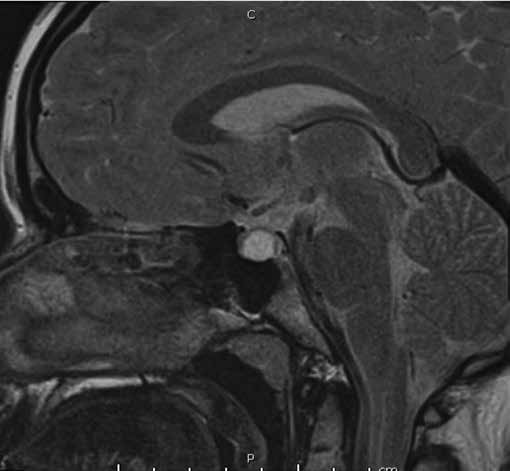

Figura 1a. RM de si a lla turca contrastada con gadolinio. Corte sagital en T1. Cortes 2.5 mm. Se señala región selar.

Se informa a continuación los estudios de imagen. Ecografía ginecológica (estudio previo indicado por ginecología): útero de forma y tamaño normal que mide 52 x 21 x 29 mm, endometrio de 5 mm, ovario derecho 25 x 18 mm, ovario izquierdo 28 x 17 mm. RM de silla turca: glándula hipofisaria aumentada de tamaño que mide 1,0 cm de altura, 1,9 cm de ancho, 1,2 cm anteroposterior, imagen de comportamiento quístico en las diferentes secuencias con realce homogéneo del parénquima glandular que rodea la lesión quística y se mantiene hipointensa en T1 (Figura 1a), tallo hipofisario en la línea media, quiasma óptico y estructuras vasculares sin compresión. En T2 se aprecia parénquima glandular hiperintenso (Figura 1b). Campo visual sin alteraciones.